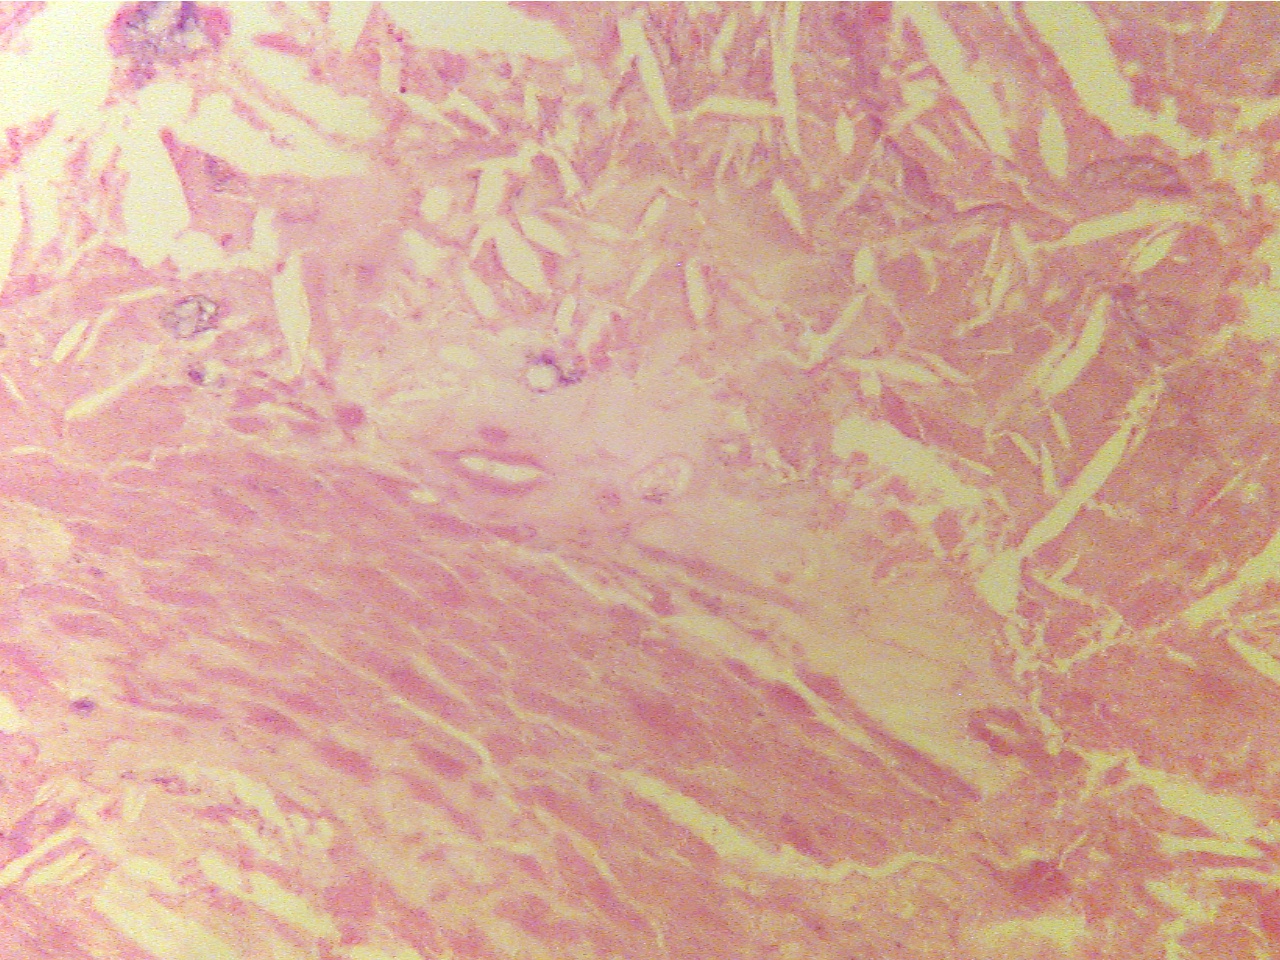

Occlusive lesion

(40X1.0 - c1)

Lumen at far left of center, crystalline lesion fills center

Fibrous plaque (100X2.0 - c1)

Plaque replaces intima and smooth muscle (100X2.0 - c2)

Layers are areolar tissue (left), externa (red collagen

Amorphous

acellular material (upper left) and cellular

fibers), smooth muscle (thin red middle layer), tunica

and

fibrous plaque (center) replace intima and smooth muscle,

intima (blue granular layer), fibrous plaque

(thick, pink),

externa (collagen fibers) remains at lower right

endothelium (thin layer along lumen), lumen (at right)

Center of plaque (100X2.0 - c3)

Endothelium (400X2.0 - c4)

Center of amorphous acellular

region

Normal endothelium (lower right bordering lumen), plaque

of plaque, much of which appears crystalline

(right, underlies endothelium), lumen (left),

damaged

endothelium with adhering RBCs (middle and top)